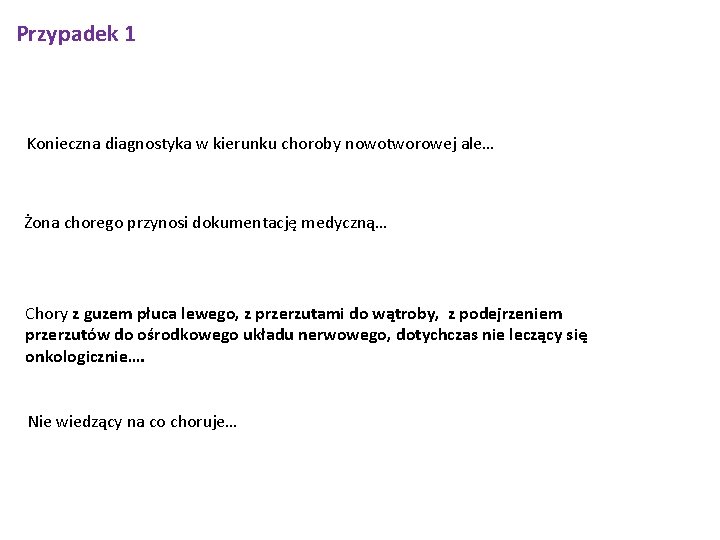

Przypadek 1 Konieczna diagnostyka w kierunku choroby nowotworowej ale… Żona chorego przynosi dokumentację medyczną… Chory z guzem płuca lewego, z przerzutami do wątroby, z podejrzeniem przerzutów do ośrodkowego układu nerwowego, dotychczas nie leczący się onkologicznie…. Nie wiedzący na co choruje…

Przypadek 1 W trakcie hospitalizacji włączono antybiotykoterapię empiryczną i wyrównywano zaburzenia wodno-elektrolitowe i kwasowo zasadowe. Pomimo zastosowanego leczenia stan chorego ciągle się pogarszał. 21/08/2015 o godzinie 13: 30 doszło do zatrzymania krążenia w mechanizmie asystolii, wobec stanu ogólnego chorego i towarzyszących chorób (rozsiana choroba nowotworowa) i złego rokowania nie podejmowano czynności reanimacyjnych. 2015 -08 -15 2015 -08 -16 2015 -08 -18 2015 -08 -20 GFR (CKD-EPI): 23. 5 [ml/min/1, 73 m] norma: (>60) Troponina T hs: 39 [ng/L] norma: CK-MB mass: 14. 70 [ng/ml] norma: (<4. 94) GFR (CKD-EPI): 25. 3 [ml/min/1, 73 m] norma: (>60) GFR (CKD-EPI): 23. 4 [ml/min/1, 73 m] norma: (>60) GFR (CKD-EPI): 17. 7 [ml/min/1, 73 m] norma: (>60)